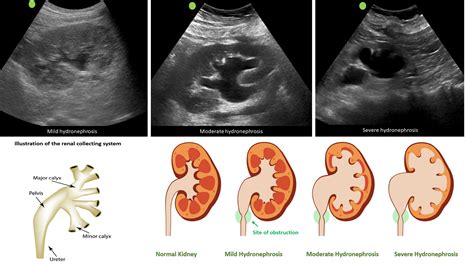

The Pocus Medical Abbreviation refers to Point-of-Care Ultrasound, a diagnostic technique that allows healthcare providers to perform ultrasound examinations at the patient's bedside. This method is particularly useful in emergency settings, intensive care units, and other clinical environments where immediate diagnostic information is crucial. Unlike traditional ultrasound procedures that are often performed in specialized radiology departments, Pocus can be conducted by trained clinicians directly at the point of care.

• Emergency Medicine: In emergency departments, Pocus is used to quickly assess conditions such as abdominal pain, chest pain, and trauma. It helps in making rapid diagnostic decisions, which can be life-saving.

• Internal Medicine: For internal medicine practitioners, Pocus is useful in evaluating conditions like pleural effusions, ascites, and deep vein thrombosis.

• Limited Diagnostic Capabilities: Pocus is not a replacement for comprehensive ultrasound examinations performed by radiologists. It is primarily used for quick assessments and initial evaluations.